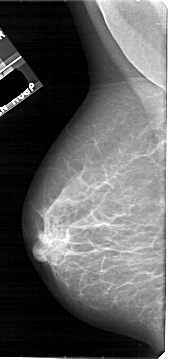

A_1922_1.RIGHT_MLO

RIGHT_MLO LINES 5101 PIXELS_PER_LINE 2671 BITS_PER_PIXEL 12 RESOLUTION 43.5 OVERLAY